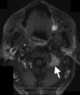

Metastasis to spine

Bone metastases, or osseous metastatic disease, is a category of cancer metastases that results from primary tumor invasion to bone. Bone-originating primary tumors such as osteosarcoma, chondrosarcoma, and Ewing's sarcoma are rare. [Source: Wikipedia ]